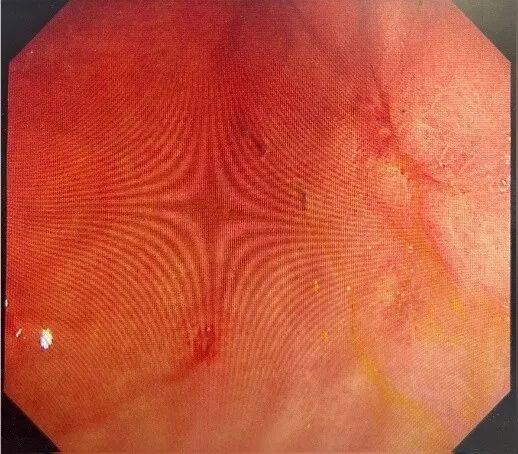

一位68岁中老年女性患者,主因“间断上腹部绞痛3天”前来就诊,患者自述3天前进食较多山楂等食物后间断出现上腹部绞痛、夜间为甚,无恶心呕吐、无腹泻、无发热;无头晕头痛、无胸闷胸痛,纳少,眠一般,二便可。入院后完善相关检查,胃镜提示:胃底、体粘液池可见大量暗红色内容物,腔内可见一枚大小约8*7cm胃石,另见大量食物残渣,影响观察。质稍软,予以异物钳、圈套器勒扎,石体成若干小块。胃角可见一巨大溃疡,予内镜下处理。

明确诊断后予抑酸、溶石、补液等对症处理,2周复查胃镜提示:胃多发溃疡(H1期)。胃底、胃体黏膜光光滑,胃石已溶解消除。

2025-12-11 胃镜